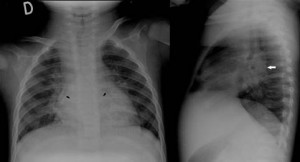

Después de la sorpresa inicial, se detiene a mirar la radiografía. ¿Qué puede ver en ella?